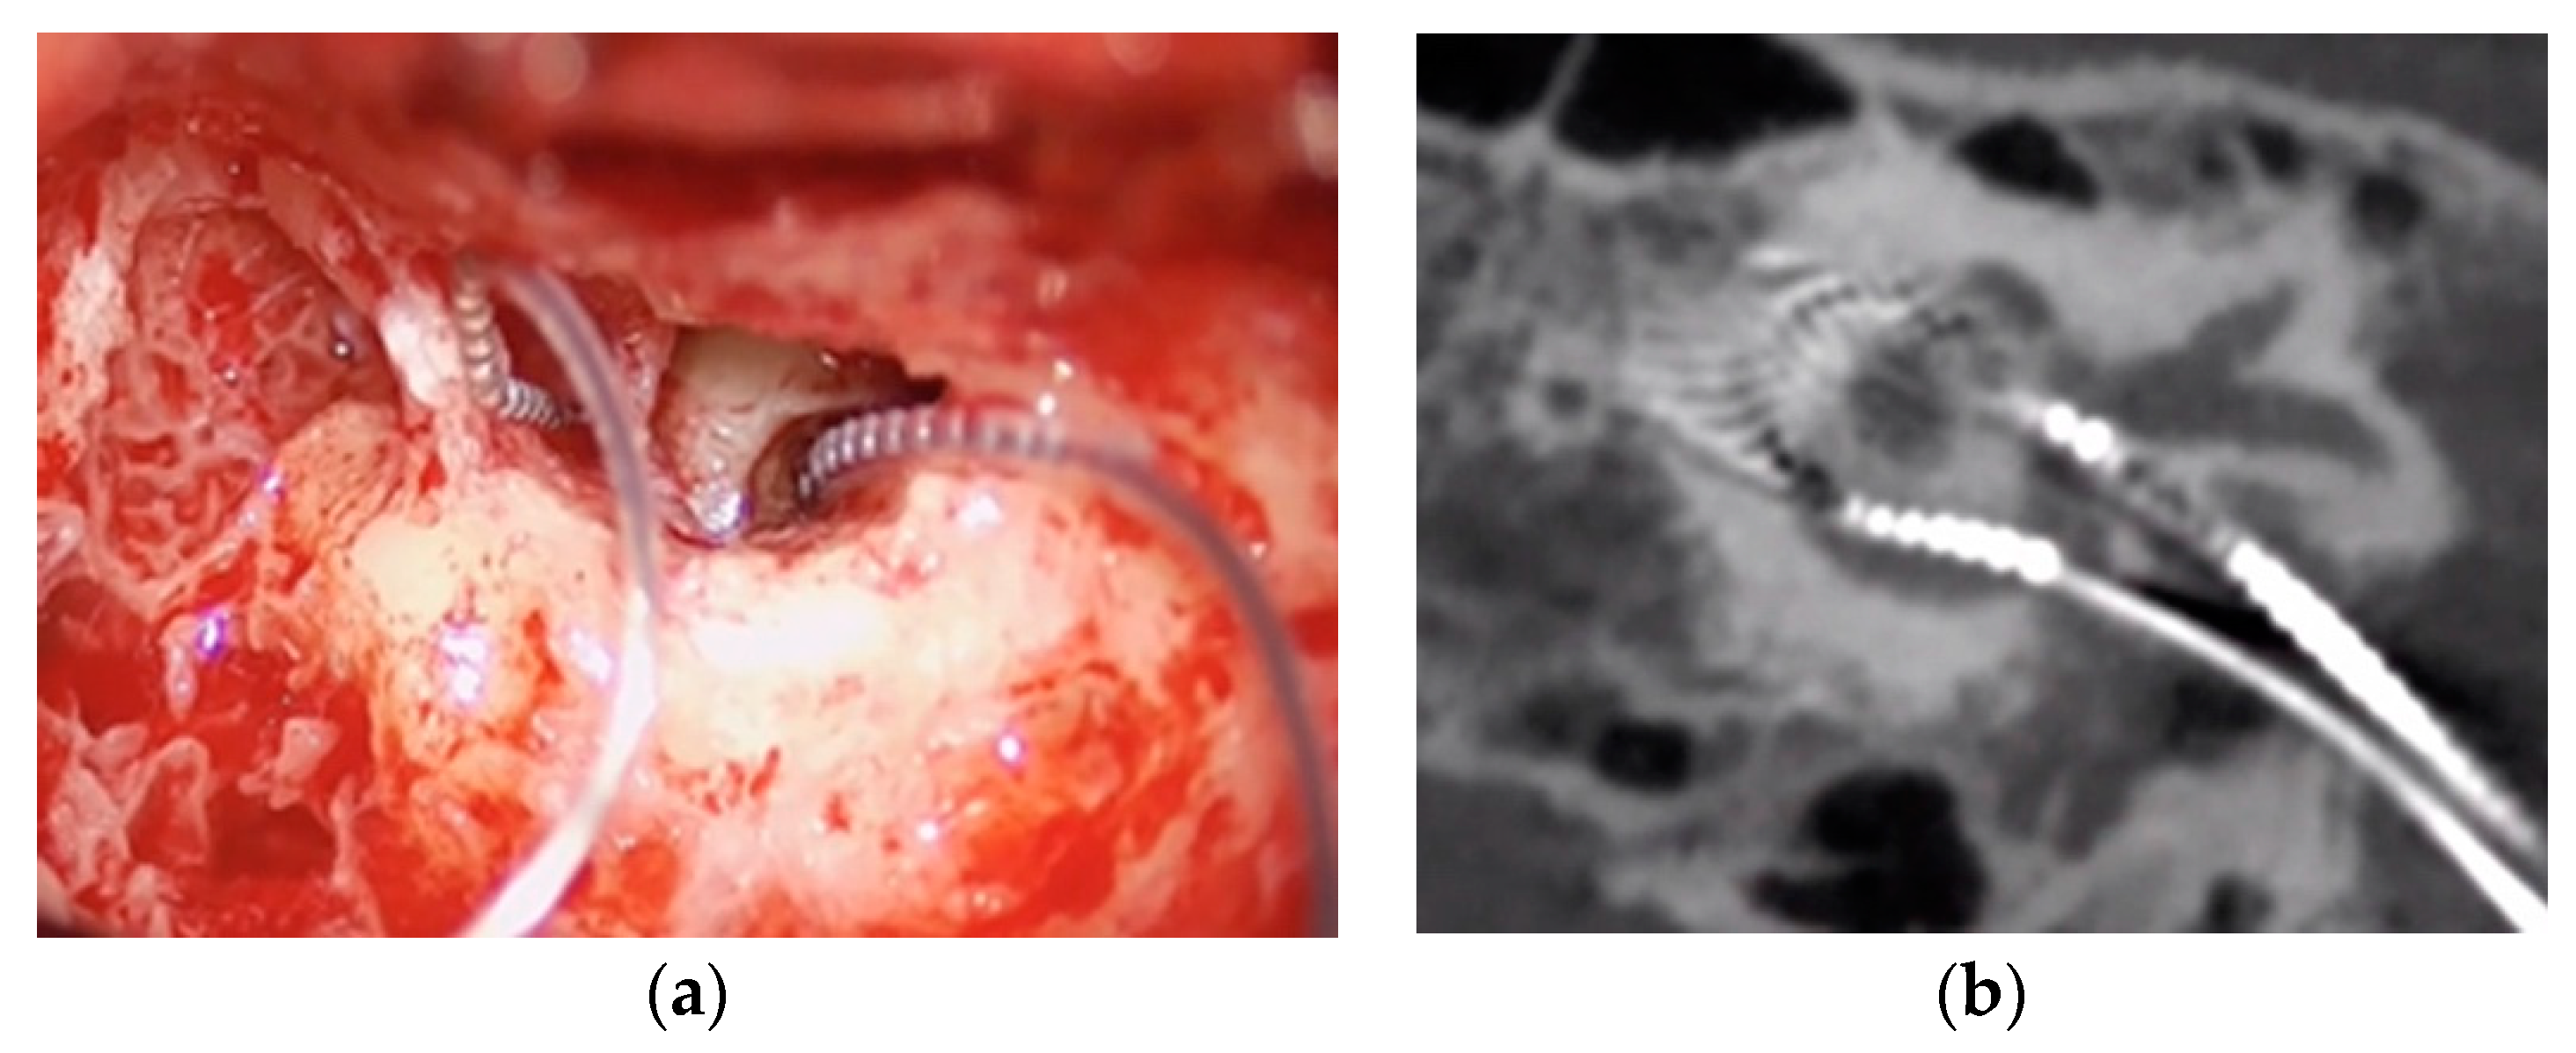

The same surgeon performed all procedures (A.R.M.). Enlarged retroauricular approach was performed. Then, after identifying the temporalis muscle, a flap was developed following the same principles as in standard CI surgery. As cochlear implantation was performed simultaneously, posterior tympanotomy was performed at this time with a clear exposure of the long process of incus, stapes and oval window. CI was inserted first. Once it was inserted and tested, VI was inserted. Opening of the vestibule was performed by performing a 0.5 mm stapedotomy medial and inferior to the anterior crura of the stapes in order to reach the closest area to inferior vestibular nerve afferent near the saccule macula, inserting the 3 first contacts of the vestibular component (Figure 2a).

During the postsurgical stay, CT scans and 3-D reconstruction were performed to check the placement and orientation of both electrodes (Figure 2b).

Figure 2. (a) Surgical image of electrodes’ position; (b) CT postoperative electrode position.